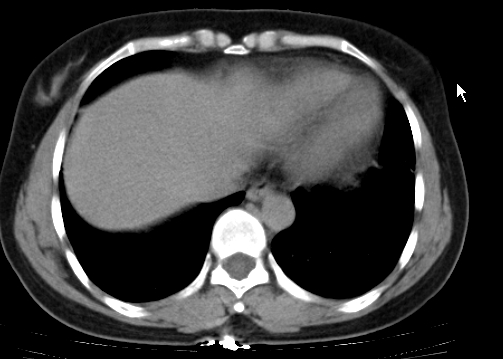

标题: CT25227:背部疼痛伴双侧胸壁痛2月,食欲差。 [打印本页]

标题: CT25227:背部疼痛伴双侧胸壁痛2月,食欲差。

肺结核并胸椎结核?请各位高手指教。

考虑胸椎结核并椎旁软组织肿胀。

椎旁软组织肿胀。

考虑胸椎结核并椎旁软组织肿胀。 支持